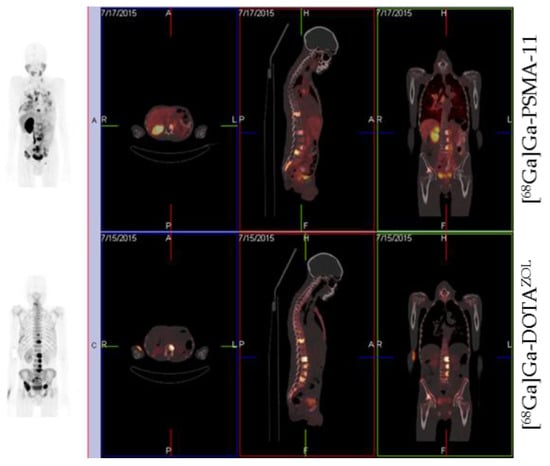

) (6.9 ± 0.1 MBq, n = 4) and [177Lu]Lu-DOTAZOL (

) (3.7 ± 0.1 MBq, n = 4) in healthy Wistar rats 60 min p.i.